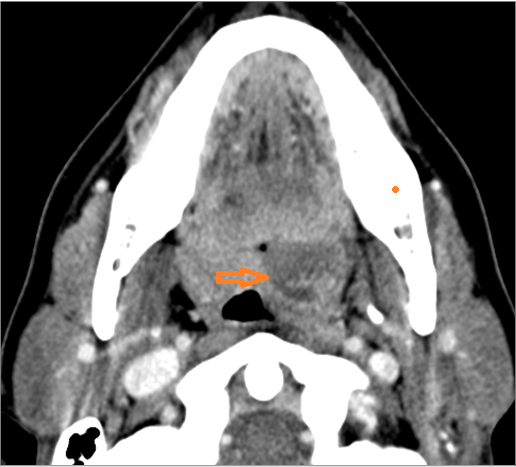

There is abscess relatively centrally within the lymphoid tissue of the palatine tonsil. [Yes/No]

There is abscess at the periphery of the lymphoid tissue of the palatine tonsil within the potential peritonsillar space. [Yes/No]

There is edema within the fat of the adjacent parapharyngeal space. [Yes/No]

There is abscess within the fat of the adjacent parapharyngeal space. [Yes/No]